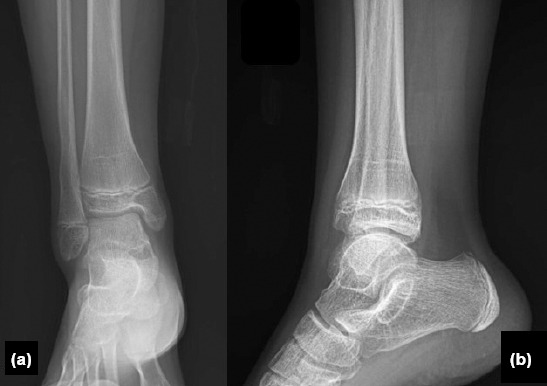

Background: Medial distal tibial Salter-Harris Type 3 and Type 4 epiphyseal injuries, also known as McFarland fractures, pose significant risks due to their potential to damage the growth plate and cause long-term joint deformities. Surgical treatment is commonly performed to restore joint congruity; however, there is no clear consensus on whether surgical or conservative treatment yields better outcomes. This study aimed to evaluate the mid-term clinical and radiological outcomes of surgical treatment in patients with McFarland fractures.

Methods: This retrospective study analyzed outcomes of 13 patients, aged 6-17 years, who underwent surgical treatment for McFarland fractures between 2021 and 2023 at a Level 1 Trauma Center. Surgical methods included screw fixation, K-wire fixation, and tension wire fixation. Outcome measures included radiological deformity assessments (lateral distal tibial angle [LDTA], anterior distal tibial angle [ADTA]), range of motion (ROM), Foot and Ankle Ability Measure (FAAM) scores for functional assessment, and Visual Analogue Scale (VAS) scores for pain. Comparisons were made between the operated and non-operated limbs.

Results: LDTA and ADTA values showed minimal differences between the operated and non-operated limbs, indicating successful surgical realignment (p<0.05). Although slight ROM limitations were observed in the operated limb, high FAAM scores and low VAS scores reflected good functional recovery and effective pain management. Correlation analysis revealed a moderate positive correlation (r=0.45) between FAAM scores and ROM, and a weaker correlation (r=0.32) between FAAM scores and radiological alignment.

Conclusion: Surgical treatment of McFarland fractures resulted in favorable clinical and radiological outcomes, with minimal limitations in ROM and significant improvements in alignment and functional recovery. However, ongoing follow-up is essential, particularly in younger patients, to monitor and manage the risk of potential growth disturbances.